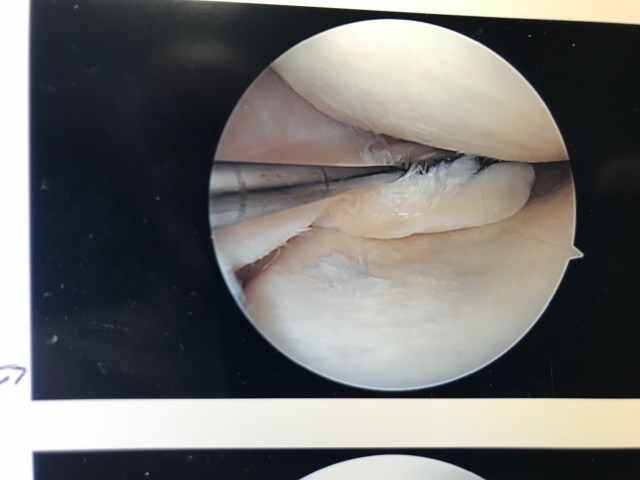

I’m not about make any money or get many likes on my Instagram for the naughty-looking pictures of the inside of my knee. Because when you look at the photo below and see the hole where my ACL used to be, the dark void tells a sad story.

And here is it. After my first tear in 2003, the orthopedic surgeon installed a cadaver part to replace the ACL I tore during a soccer match. I named the cadaver part Jake after the anonymous donor, but two years after the ACL repair surgery, the cadaver part gave out as well. Jake died all over again.

Finally the knee did start to hurt. Which led to the visit to the doctor, and the MRI that showed a chunk of meniscus torn inside my knee. That led to surgery and these before and after photos of the excision being performed on a torn meniscus. What a delightful little montage of knee porn.

I find my knee porn images somewhat funny. If these were dick pics or a closeup of some woman’s vagina, this blog would be Rated R and the content considered scandalous. The second image does look quite a bit like a shaved mons venus. But since these images were actually taken inside my knee, they have no scandal value at all. In fact, they mean very little to anyone but me.